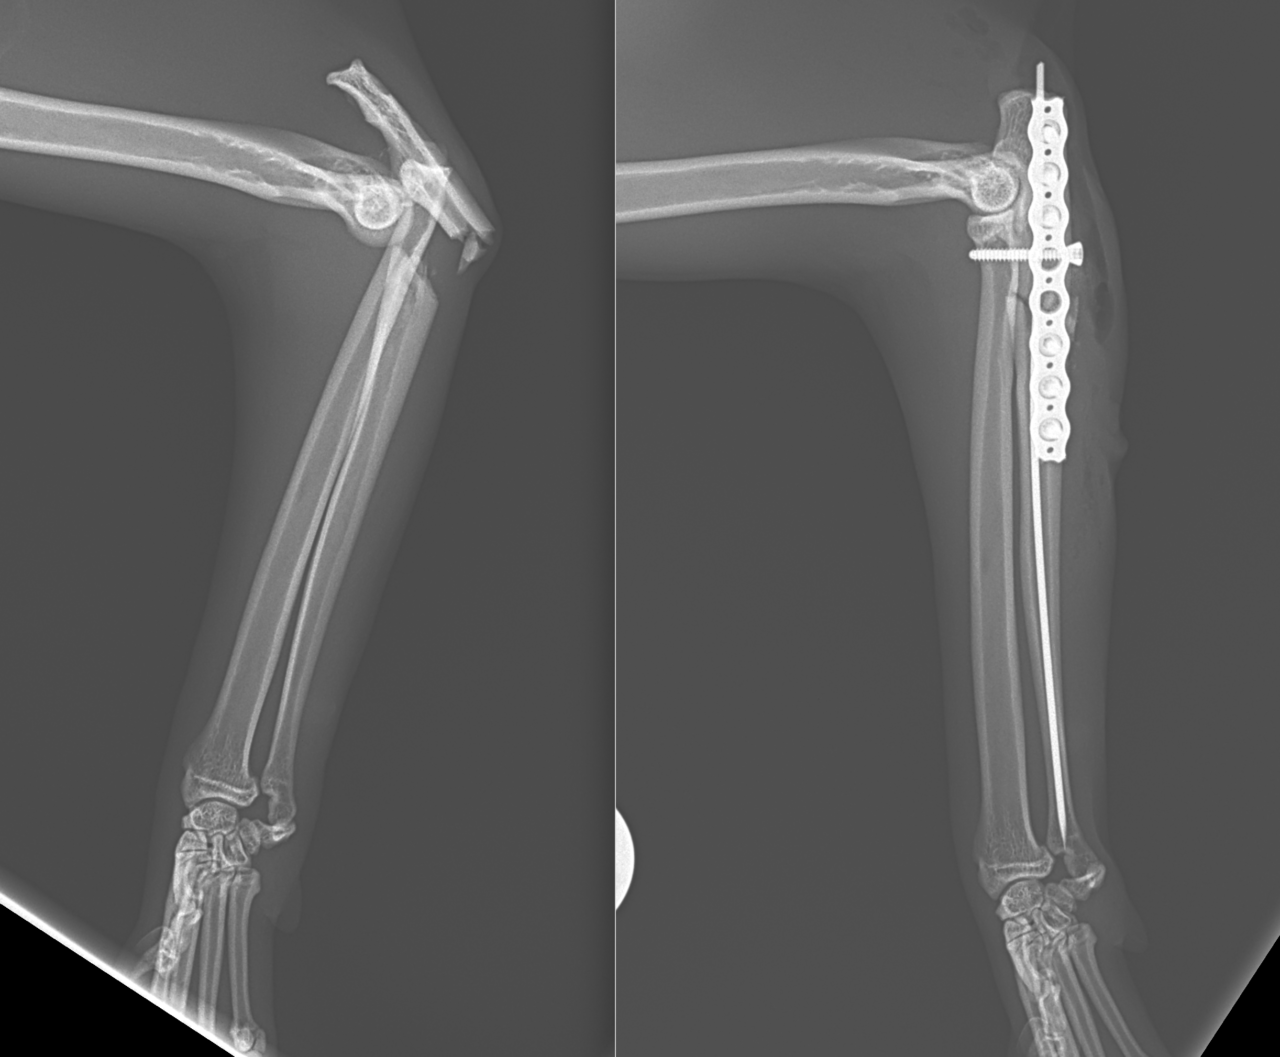

猫ちゃんがお家から居なくなり、探していたところお庭でうずくまって居るところを発見されました。かかりつけの動物病院で両側のモンテジア骨折と診断されました。(原因は落下事故と判明)外科的整復のため当院へ搬送されました。橈骨頭を整復したのち、尺骨にIM pinを刺入、2.0-Locking Plateで固定術を行いました。橈骨頭へ尺骨側からポジションスクリューで固定を併用します。このスクリューは約4週間を目安に抜釘を予定しています。